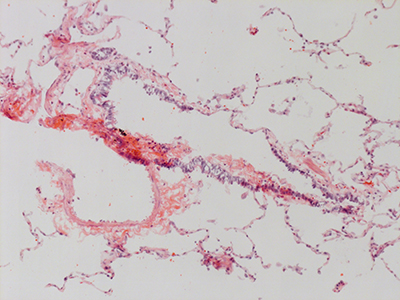

31 Year Old Adult Human Lung D0036 H&E